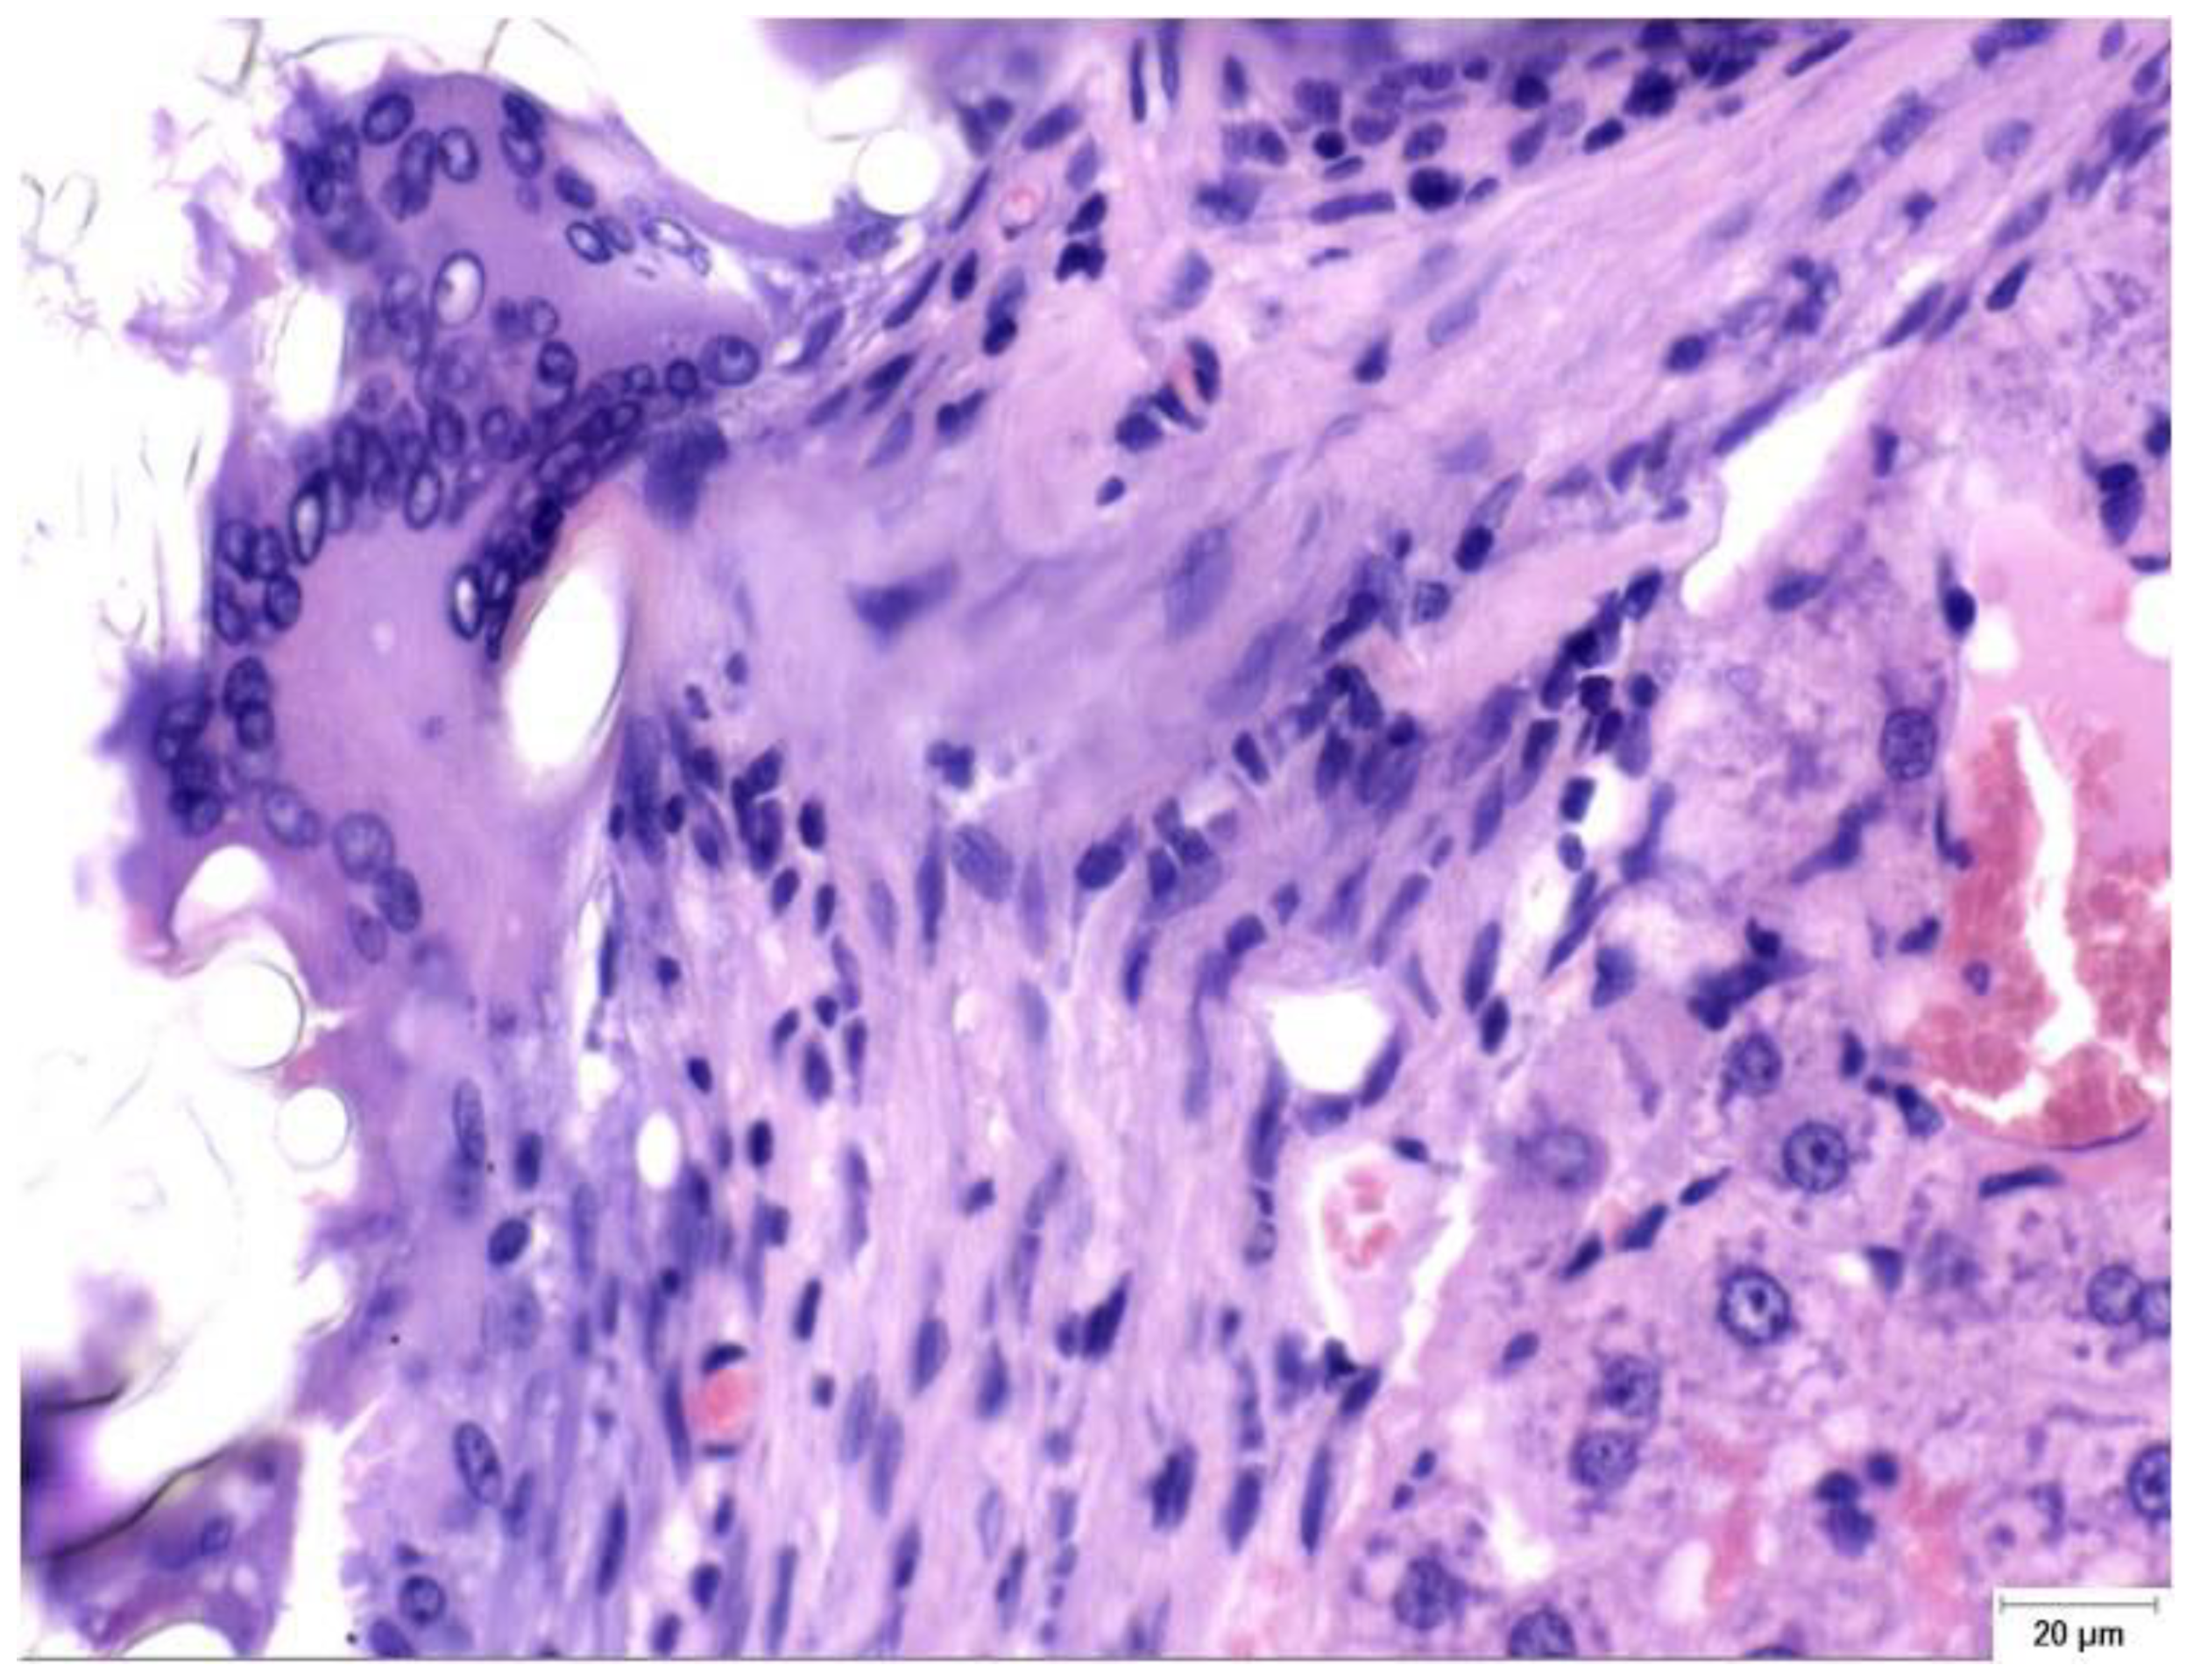

Figure 2.

Granulomatous foreign-body reaction observed in the perihepatic tissue from a rat in the Study group (CA + PLA) at PO day 150 (Hematoxylin and Eosin stain, ×40 magnification). A dense infiltrate composed predominantly of histiocytes and scattered lymphocytes surrounds the residual biomaterial. Multinucleated foreign body-type giant cells are evident within the fibrotic stroma, indicating a sustained chronic inflammatory response to the adhesive compound. Scale bar (right lower corner): 20 µm.